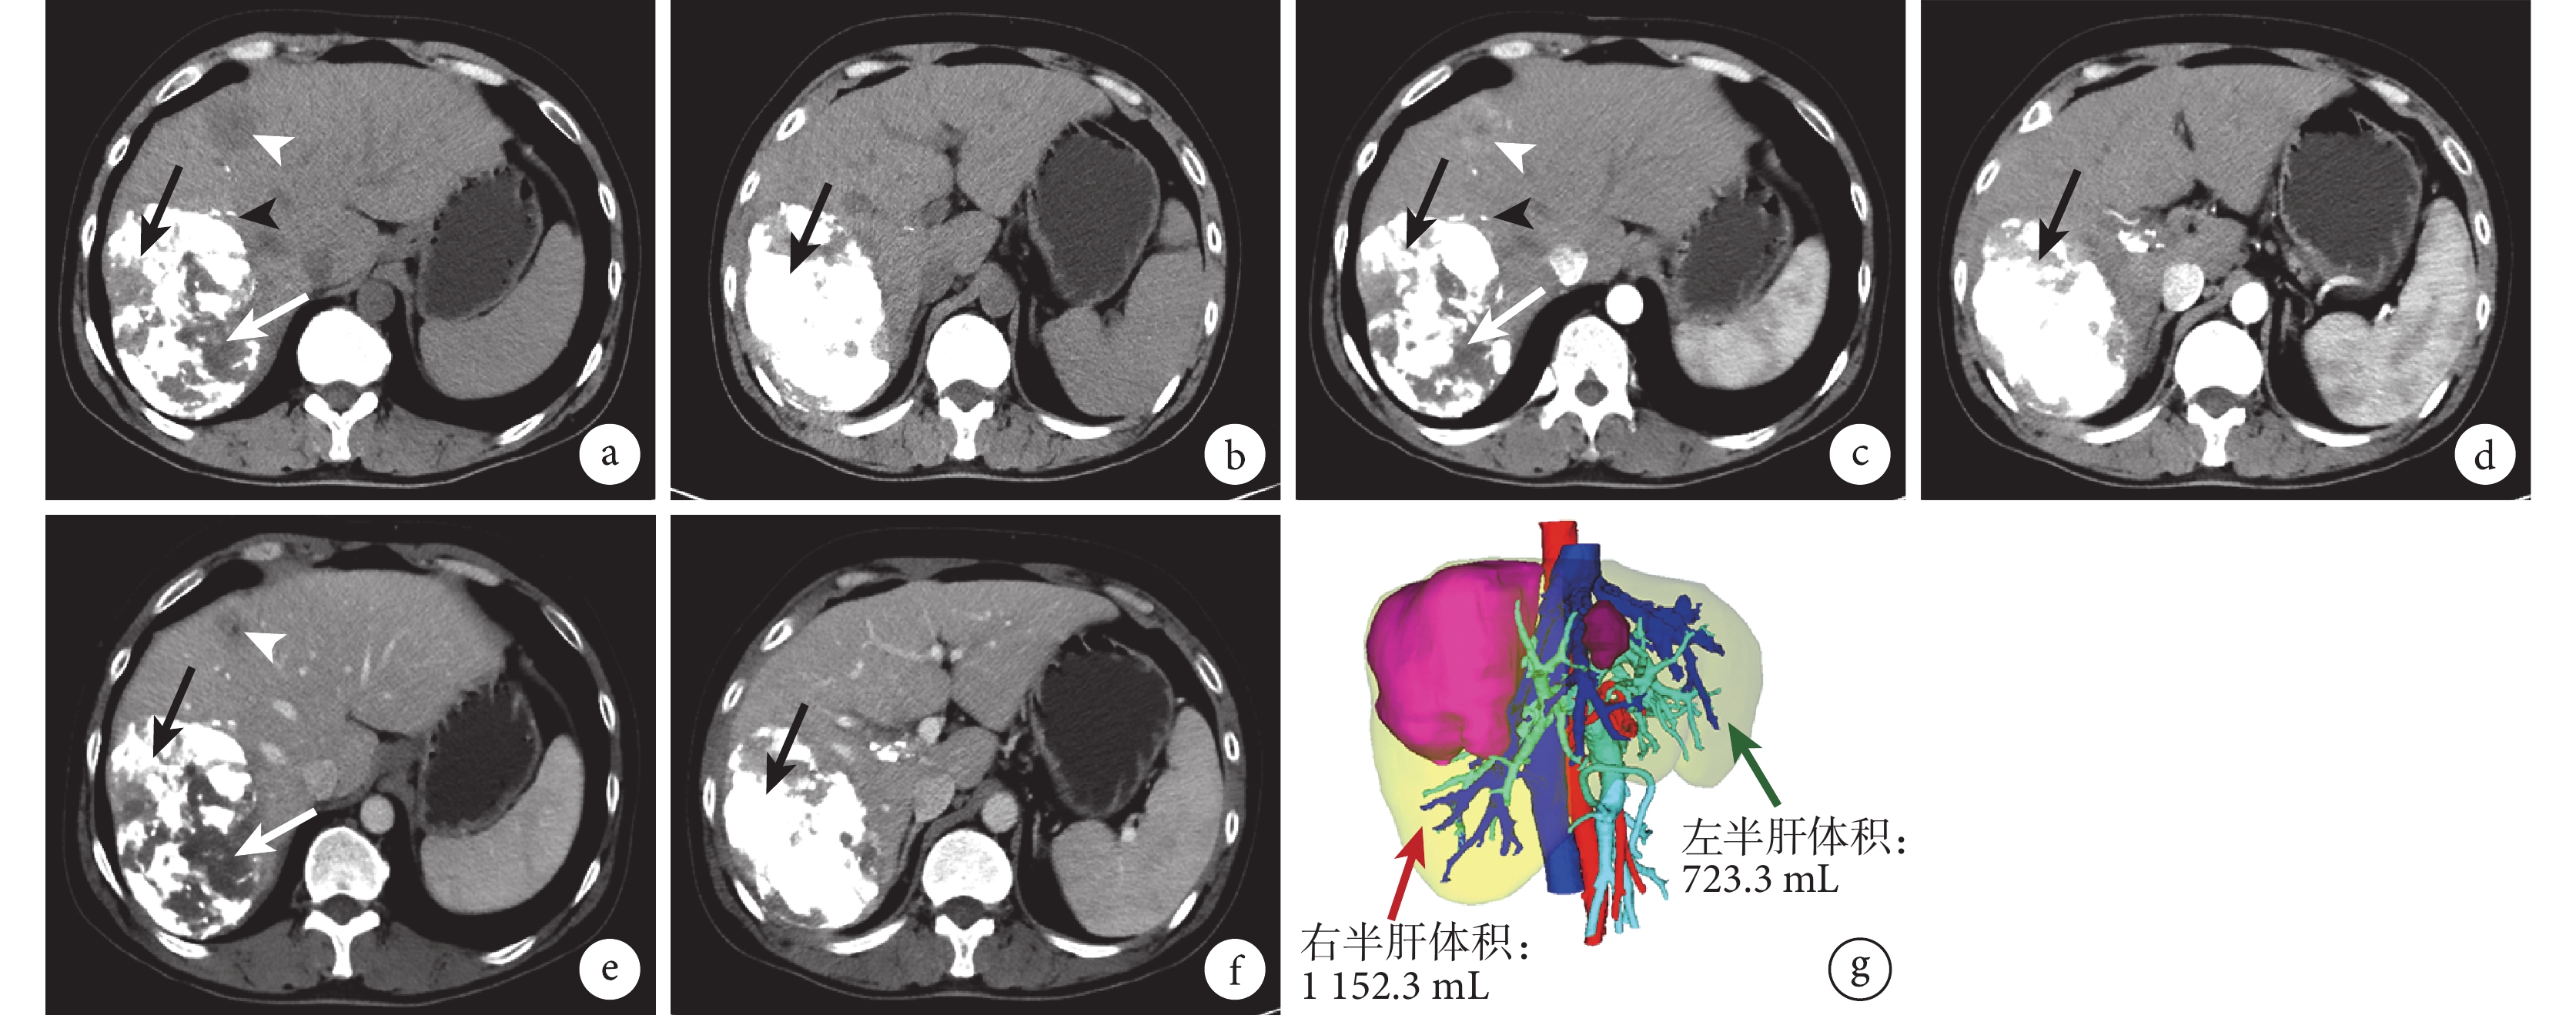

a~f:平掃(a 和 b)、動脈期(c 和 d)及門靜脈期(e 和 f)圖像示右肝腫瘤明顯縮小,右肝腫瘤內大部分碘油沉積良好(黑箭),局部碘油沉積差(白箭),腫瘤周圍衛星小結節可見碘油沉積(黑箭頭),左肝腫瘤碘油沉積差(白箭頭)、瘤體稍縮小,左肝明顯增生;g:3D 重建示左肝體積增生至 723.3 mL,約占全肝體積的 38%